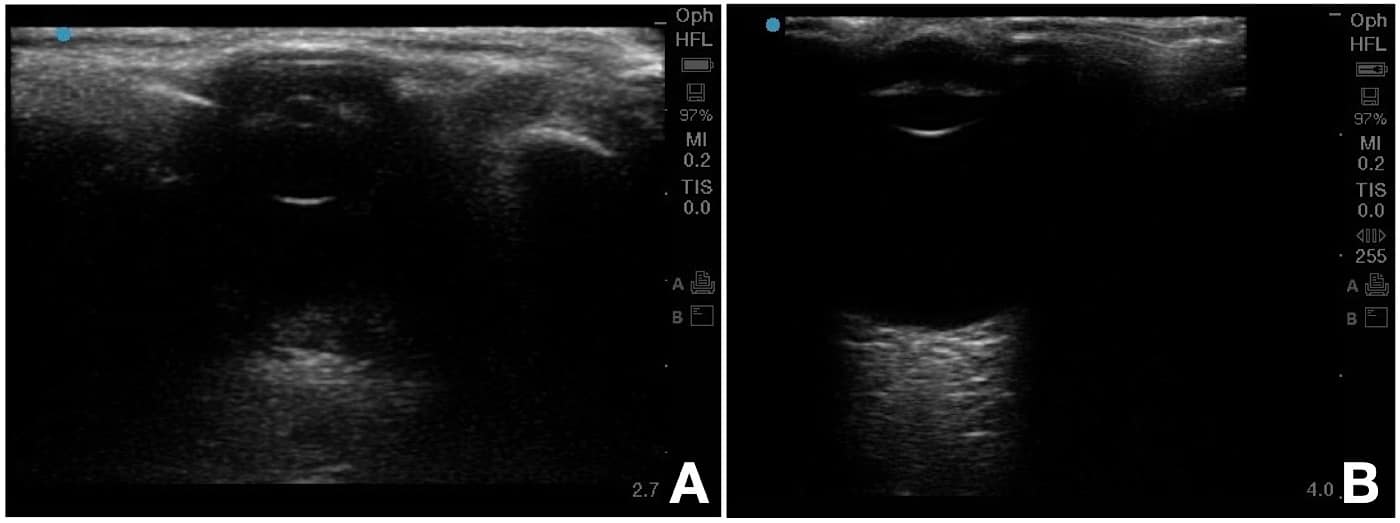

- Scan protocol: Ultrasound examination is carried out at two axes perpendicular to each other.

- Horizontal Scan: Probe is placed in a line joining both canthi, i.e, horizontal axis (Figure 4A).

- Vertical Scan: Probe is placed in a plane perpendicular to first plane, ie, vertical axis (Figure 4B).

- Measurements are taken in both axes, and a mean of ONSD in both transverse and vertical axes is taken as the final measurement representative of ONSD (Figure 5).